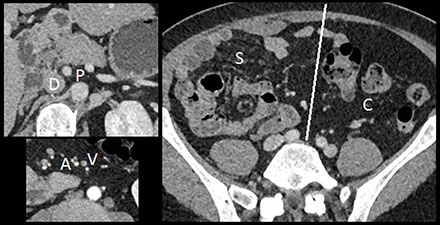

– Intestinal nonrotation: the small bowel was right-sided (S), the colon was left-sided (C), the superior mesenteric artery (A) was to the right of the vena (V), and there was no midline crossing by the duodenum (D) under the aorto-mesenteric junction (P) (Figure 3).